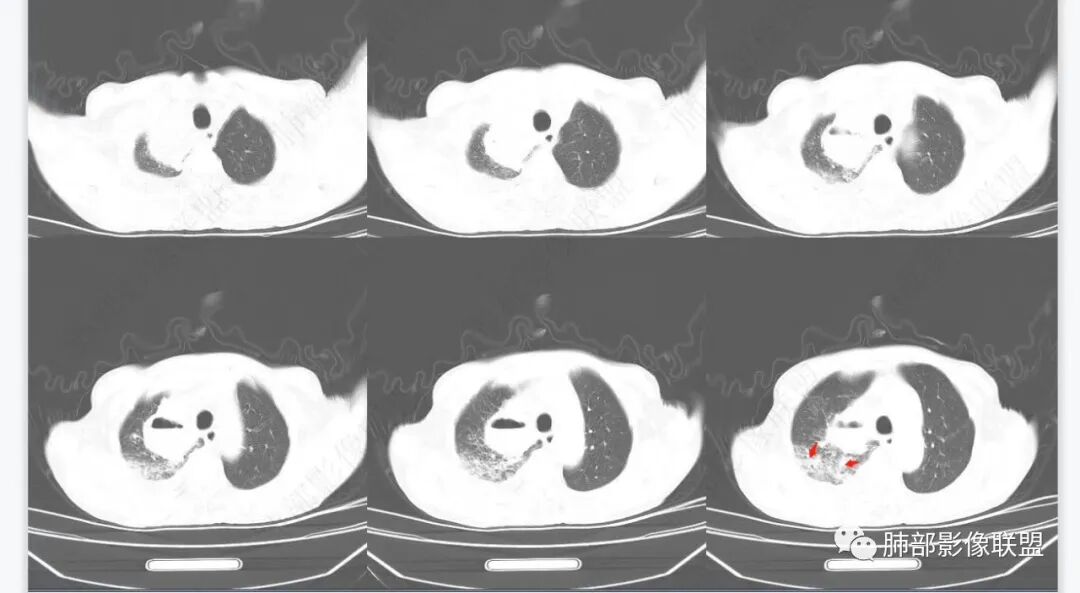

1月后,发热再次入院

这些新发的

合并有胸水

出现液气平面

治疗一周后复查

周围干净了,液平小了

壁似乎均匀了

南边  :

可惜没薄层

窗宽不够窄

看不太清

治疗两周,病灶内气体没了

就目测看内壁还是清楚的

我就在想这个感染如何继发的?

近端的支气管如何改变?

感染了:腔内就出现液气平面,附近大片高密度影

治疗后,腔内含气病灶少了

说明支气管通畅——狭窄——堵塞

我怀疑是不是堵塞口通了,腔内的坏死物播散到附近肺组织

抗炎后转后,支气管又收缩,堵了